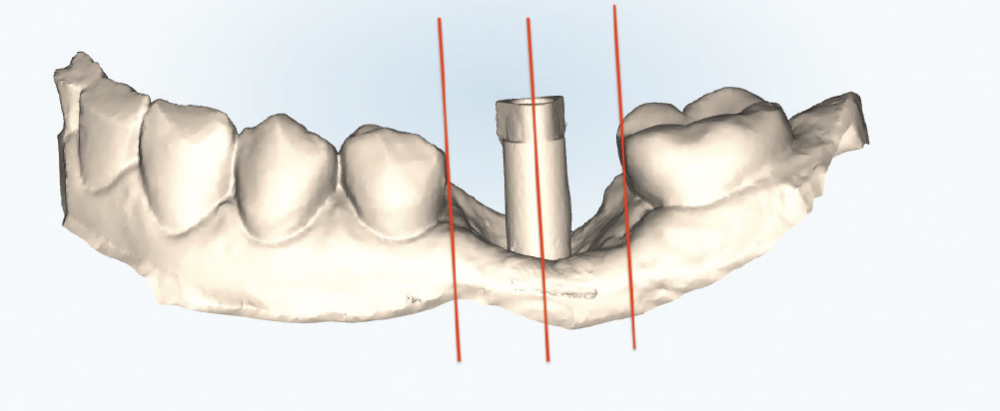

Thoroughly Scan the Scan Body Geometry

Thoroughly Scan the Scan Body Geometry. Complete, high-resolution capture of the scan body is non-negotiable. This is how laboratory software determines the precise three-dimensional position and angulation of the implant. The software matches the scanned scan body with its library file to establish the implant location in space. Scan from multiple angles to ensure all identifying features and surfaces are captured, as incomplete scan body data leads to misaligned restorations regardless of how perfect the rest of the scan appears. Verify that all reference markers, grooves, or geometric features are clearly visible in the acquired scan.

Verify the Path of Draw

Verify the Path of Draw. Creating clear guide planes on adjacent teeth establishes a predictable path of insertion and helps minimize black triangles, which is critical for both single-implant and multiple-unit cases. Create an intentional path of insertion before scanning to guide laboratory fabrication, carefully considering the relationship between the long axis of the implant and the adjacent contacts. This foundational step ensures the restoration can be inserted and removed without binding or damaging adjacent structures.